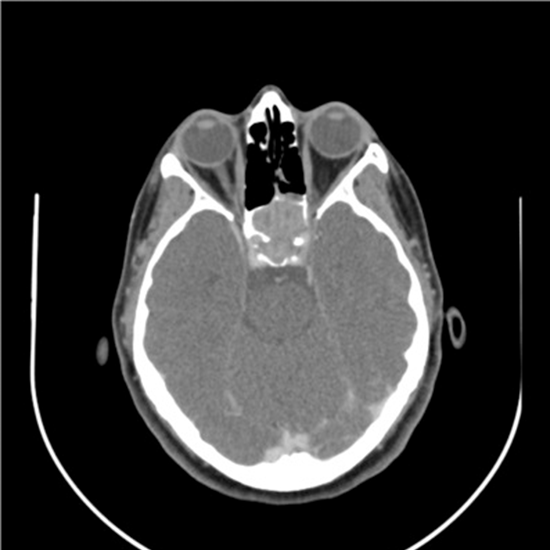

CT (Computed Tomography) Sella Axial and Coronal is an imaging procedure used to obtain a picture of the front- the back view as well as a top-bottom view of pituitary sella. This helps detect the problems and abnormalities of pituitary sella.

Why is CT Sella Axial and Coronal Done?

Doctors recommend this procedure to detect

• The abnormalities in sella such as empty sella syndrome

• Pituitary Tumor

• Cause of decreased vision

• Problems that are affecting the pituitary gland or sella turcica.

• shrunken/flattened pituitary gland.